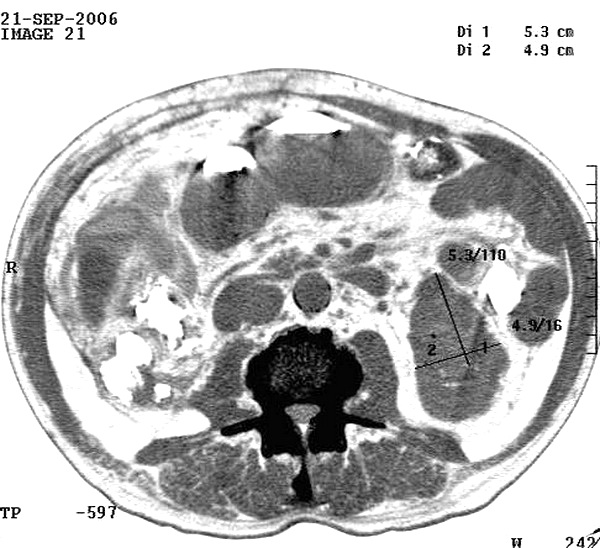

Рис.1. Положение больного с хронической сердечной недостаточностью.